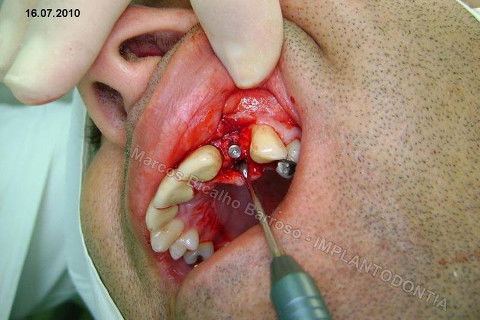

Este caso tem o objetivo de demonstração da técnica que normalmente sigo ; em casos onde ocorre fratura da raiz e consequentemente abscessos, com ou sem formação de fístula. Neste caso fiz a exodontia com preenchimento do alvéolo com biomaterial (osso bovino liofilizado + coágulo do paciente). Após 90 dias, mais ou menos, instalei o implante. Esperei mais 4 meses e realizei ontem (12/11/2010) a instalação do cicatrizador com o cuidado de preservar tecido mole, sem remoção de material, apenas afastando gengiva e "enrolando" a sobra de mucosa em direção a face vestibular, para promover conservação de papila futuramente. Se ocorrer excesso de papila, sem problema, remove-se um pouco, mas a intenção é não deixar faltar, o que resultaria em indicação para enxertos gengivais.